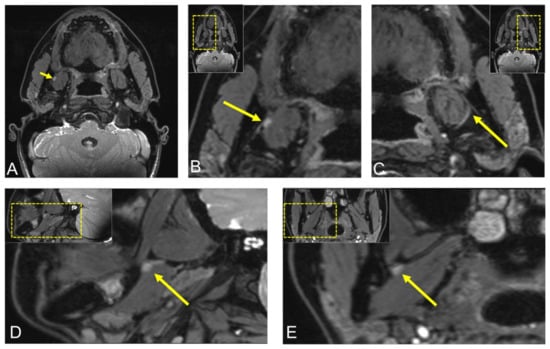

2.1. Case 1